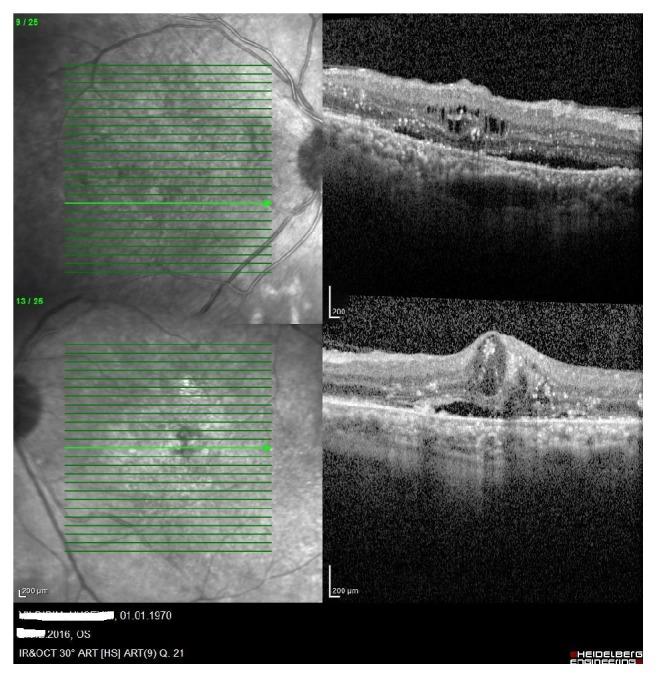

Dexamethasone implant, 0,7 mg (Ozurdex, Allergan, Inc., Irvine, CA, USA), is drug mostly used in the treatment of the diabetic macular edema and edema related to retinal vein occlusion. By reporting this case we aimed to report a new side effect of 0.7 mg intravitreal dexamethasone implant that has not been reported in the literature before.

地塞米松植入剂,0.7毫克(奥助得,爱力根公司,美国加利福尼亚州欧文市),是一种主要用于治疗糖尿病性黄斑水肿及视网膜静脉阻塞相关水肿的药物。通过报告该病例,我们旨在报道一种0.7毫克玻璃体内注射地塞米松植入剂的新副作用,此副作用此前尚未见文献报道。